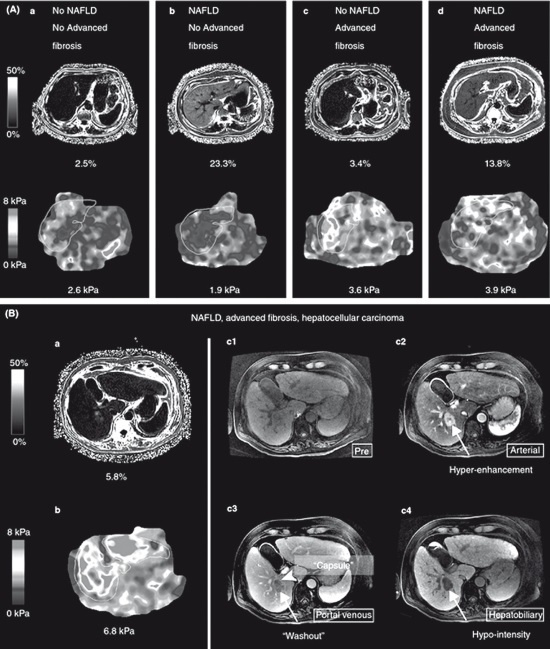

МРТ печени с фазовым контрастированием позволяет количественно оценить степень жировой инфильтрации. Очаги снижения интенсивности на Т1-взвешенных изображениях могут свидетельствовать о локальном накоплении жира. У пациентов с сахарным диабетом 2 типа в качестве метода скрининга НАСГ рекомендуется МРТ с определением степени жировой инфильтрации посредством расчета протонной плотности жира и определение степени фиброза печени посредством МРТ-элластограммы [16].

Рис. 36. МРТ-элластограмма у пациента с сахарным диабетом 2 типа [16]